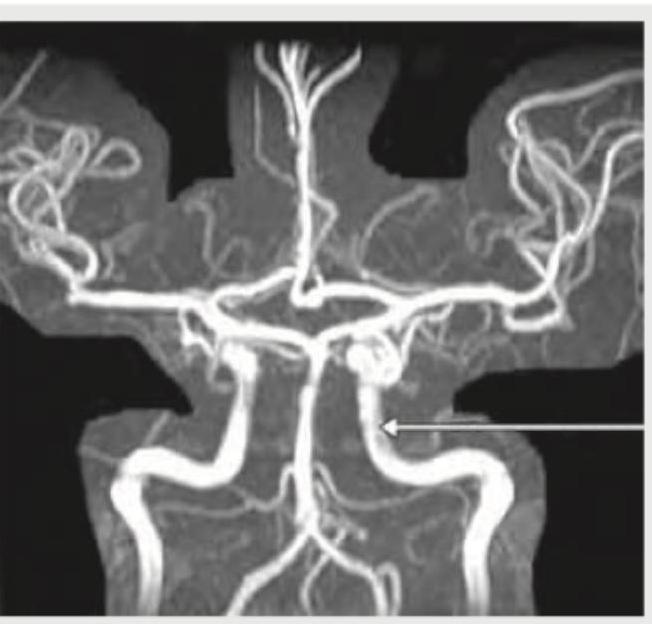

What is the name of the marked blood vessel shown in brain circulation?

Explanation: ***Posterior communicating artery*** - The arrow points to a vessel connecting the **anterior circulation** (internal carotid artery system) with the **posterior circulation** (vertebrobasilar system) within the **Circle of Willis**. - This specific location and function are characteristic of the **posterior communicating artery**, which typically arises from the internal carotid and joins the posterior cerebral artery. *Middle cerebral artery* - The middle cerebral artery is a large artery that branches off the **internal carotid artery** and typically extends laterally and superiorly to supply a large part of the **cerebral hemispheres**. - It would appear more prominent and more laterally positioned, not forming a direct "communicating" link in the central Circle of Willis as shown. *Internal carotid artery* - The internal carotid artery ascends from the neck into the skull and bifurcates into the **anterior and middle cerebral arteries**. - While visible in the image, the arrow is pointing to a smaller anastomotic branch, not the main trunk of the internal carotid artery. *Anterior communicating artery* - The **anterior communicating artery** connects the two **anterior cerebral arteries** at the anterior aspect of the Circle of Willis. - This is a distinct location from that indicated by the arrow, which shows a vessel connecting anterior to posterior circulation, not linking the two anterior cerebral arteries.